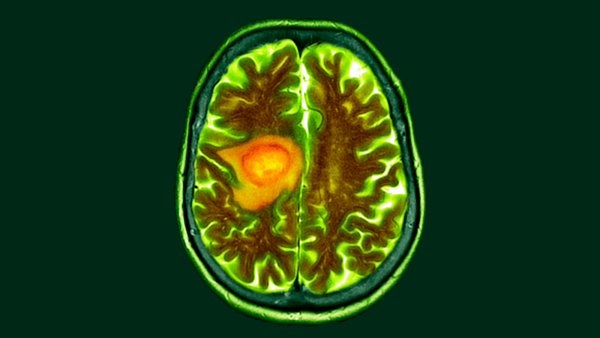

Під час розробки мРНК-вакцин для пацієнтів з пухлинами головного мозку у 2016 році наша команда під керівництвом дитячого онколога Еліаса Сайюра виявила, що мРНК може навчати імунну систему знищувати пухлини, навіть якщо мРНК не пов'язана з раком.